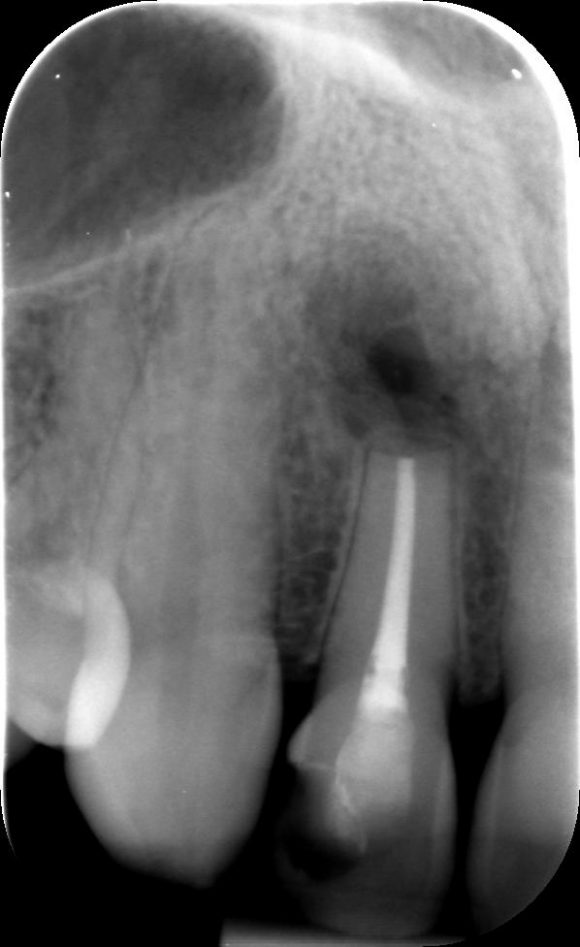

A fogciszta kezelése attól függ, hogy az milyen területen helyezkedik el. Amennyiben a gyökércsúcsnál van, úgy gyakran elhalt fogról van szó. Egy szuvas fog, egy elhalt fog vagy egy, már régen gyökérkezelt fog esetén is ugyanaz az eljárás. Először a fogat gyökérkezelni kell, mielőtt a ciszta eltávolításához fognánk hozzá.

1. A cisztás fog gyökérkezelése:

Fontos szempont a csúcsig érő és falálló gyökértömés kivitelezése. Ettől a fog a szájüreg irányából teljesen zárt, tehát több baktérium nem juthat ki a gyökércsúcs körüli csontállományba.

Egy régebben már gyökérkezelt fog esetén elsőként eltávolítják a meglévő gyökértömést, -mely rendszerint hiányos is a röntgenfelvételek szerint- majd alaposan áttisztítják a csatornákat, bemérik a hosszukat, végül pedig letömik őket.

A modern gyökérkezelés előnye az a számos digitális eszköz, mellyel pontosan felmérhető a fog állapota: pontosan meghatározható a csatornák hossza, valamint feltárhatók azok a csatornák vagy csatorna elágazások is, melyek -korábban a 2 dimenziós röntgenen- rejtve maradtak.